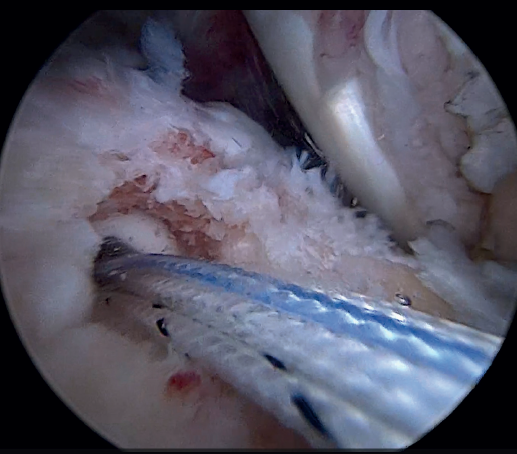

Previously, at intra-articular level, we assessed the quality of the LPB and its insertion in the supraglenoid tuberosity; from subacromial, having prepared the bony footprint on the greater tuberosity, we proceed to release the proximal portion of the tendon from the bicipital groove. The upper part of the transverse humeral ligament is sectioned to mobilize the LPB without damaging it (Figure 2). At this time, the mobility and integrity of the LPB is checked with tendon pulling forceps (Figure 3).

The glenoid origin of the LPB is preserved at all times. In the anterolateral zone of the greater tuberosity, we implant an anchor loaded with three sutures (FiberTak® 2.6 mm, Arthrex, Naples, FL, USA), more medial to the reflection zone of the LPB. To ensure correct guidance at implantation, we create a superolateral accessory portal without a cannula, close to the limit of the acromion.

Using penetrating forceps through the anterior portal, the surgeon penetrates the LPB and retrieves one of the suture threads, performing a self-locking Lasso suture in the same step. This is done with two of the three anchoring threads to ensure a correct LPB grip to the footprint of the greater tuberosity and that the tendon does not fray; we do not cut the two threads after knotting (Figures 4, 5 and 6). We also consider it very important to apply the biceps tendon, keeping it as flat and anatomical as possible, avoiding twisting or excessive distension of the tendon. Subsequently, a tenotomy of the LPB distal to these sutures is performed (Figure 7), thus allowing the LPB to function as a superior capsular reconstruction, restricting the ascent of the humeral head.